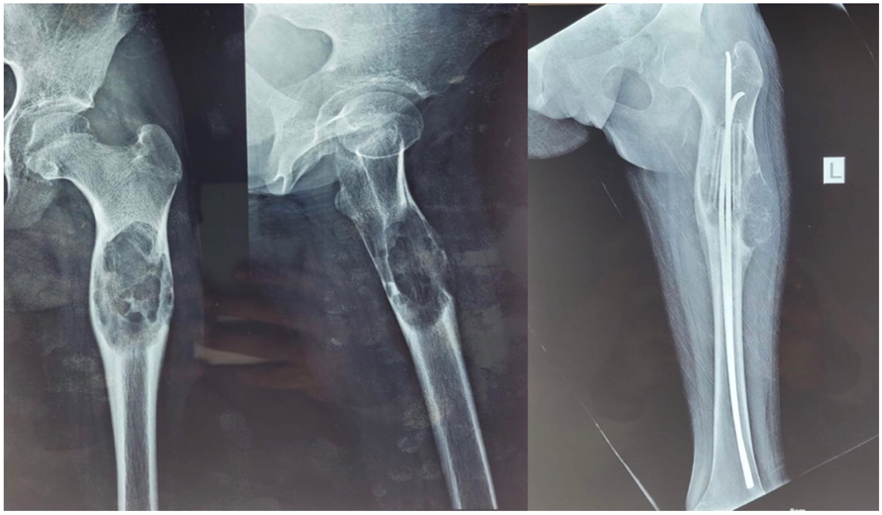

This case report follows a 13-year-old girl who present with pain in the left hip region for 2 months along with difficulty in walking. No associate significant contributory history. Radiograph was s/o a solid cystic lesion on the proximal femur. Magnetic resonance imaging (MRI) contrast scan of left thigh with femur done s/o well marginated expansile altered signal intensity lesion in proximal diaphysis of left femur with few cystic changes within with break and thinning of cortex at places with periosteal reaction around the lesion. Core biopsy was done s/o Aneurysmal Bone Cyst for which she undergone curettage of bony cyst with bone grafting (fibula) with Intra-Medullary nailing as shown in Fig. 1. Post-operatively she developed fever with wound gets infected with some discharge. Treated with higher antibiotics and daily cleaning and dressing. Fever subsided but continuous discharge from wound present.

Figure 1: Pre-operative Radiograph showing a multicasting lesion in the left proximal femur, Radiograph of post-curettage with fibula grafting with nailing.